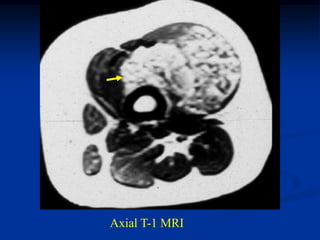

Case #1205

38 year female with

hemangioma forearm

with hypertrophic response

in subadjacent ulna

Bone scan

bone

hypertrophy

Axial PD MRI

Axial gad contrast MRI

Sagittal T-2 MRI